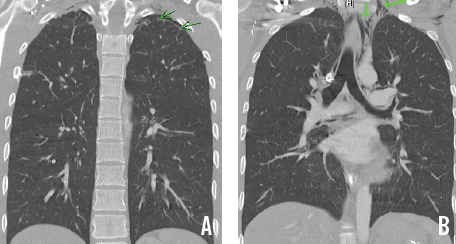

Physical examination findings were unremarkable except for mild epigastric tenderness. Urinalysis was positive for cannabinoids. Results of a serum electrolyte panel showed a potassium level of 3 mEq/L and a bicarbonate level of 27 mEq/L. Results of chest radiography and computed tomography showed a small left apical pneumothorax (A) and pneumomediastinum extending from the base of neck to the distal esophagus and laterally into the left axilla (B). Esophagography results were unremarkable.

Our patient’s pneumothorax and pneumomediastinum may have resulted from the rupture of a subpleural bulla caused by forceful vomiting.